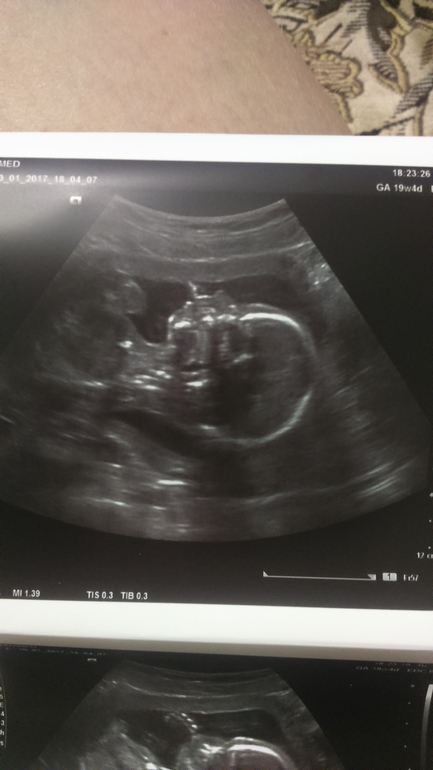

А ещё мы сегодня были на узи всей семьёй, ещё и сестричка моя.

Будет у нас сынок! муж вообще не перестаёт улыбаться))) доча сказала, что не придётся делиться игрушками, хотя очень хотела сестричку)

Вес малыша около 282 г, все в норме у нас, показали все очень подробно - вот преимущество платного узи с отдельным экраном)

где-то 18+5 на фото